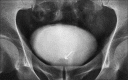

Brunn's cyst in the region of the bladder neck is a rare cause of lower urinary tract obstruction. This case describes the ultrasonographic and intra-venous urographic findings of Brunn's cyst in a 53-year-old male presenting with lower urinary tract symptoms.